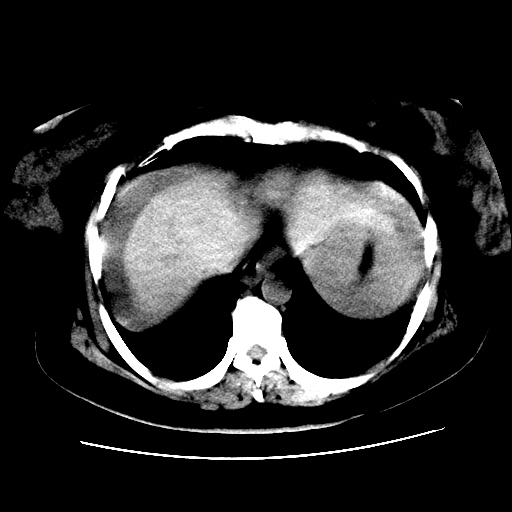

f,45y.怀孕4月晕倒,b超提示死胎,有手术结果,请展开讨论后明天告诉。

膈下-肠间隙内见气体密度影,子宫轮廓显示不清,宫腔-腹腔积液,首选考虑---子宫破裂出血。

1)宫腔妊娠。2)子宫破裂出血,腹腔及盆腔积血。

怀孕4个月晕倒,病史就这么简单?有没有腹痛呢?腹腔内有没有气体?窗宽太窄了脂肪组织与气体已不好分。如果有气体,那就是空腔脏器穿孔,如胃肠穿孔。如没有气体,就考虑子宫破裂或宫外孕破裂。正常怀孕子宫破裂很少见,有可能是宫外孕。极有可能是残角子宫怀孕破裂。腹腔怀孕破裂也有可能。

感谢同行们的高见。手术结果:子宫破裂出血。

我们的诊断是:腹、盆腔积液(考虑腹盆腔脏器破裂出血);宫腔妊娠。让人纳闷的是当时我们没有经验,现在回头看看分析:4月宫腔妊娠:1、洋膜囊不可能紧贴胎体这么小;2仔细看看子宫后壁肌层模糊不清;3腹、盆腔液体来源原因?4、45岁高龄妊娠有晕倒。由此可大胆诊断:宫腔妊娠子宫破裂出血。